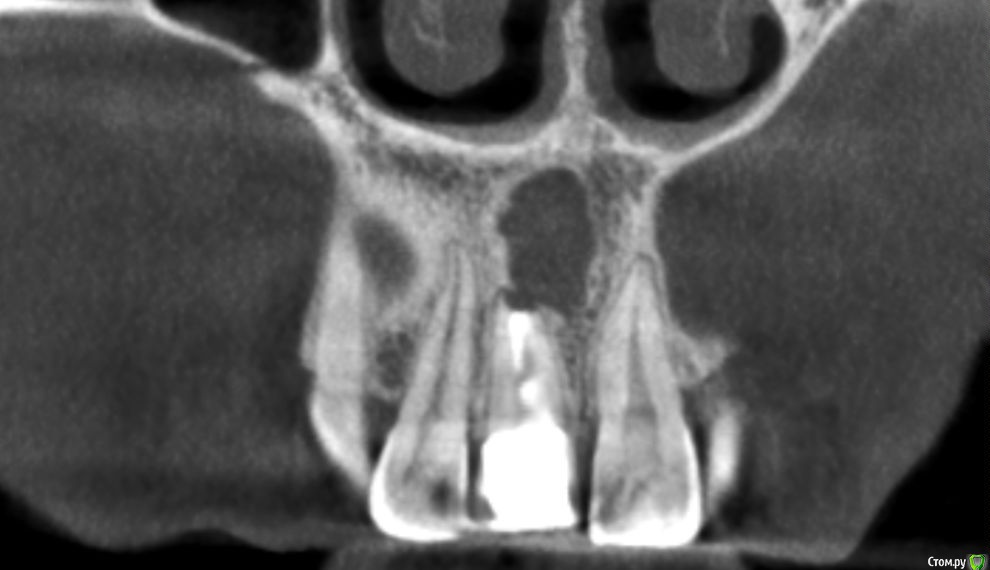

Kazankov.Egor Опубликовано 6 июля, 2018 Поделиться Опубликовано 6 июля, 2018 (изменено) Жалобы на неприятный запах изо рта, предположительно от 11 зуба. В анамнезе РВК 11 зуба.Скрины кт прилагаю. Пациент девушка, естественно, главный вопрос -эстетика. Нужна помощь по тактике. Изменено 6 июля, 2018 пользователем Kazankov.Egor Ссылка на комментарий

Kazankov.Egor Опубликовано 7 июля, 2018 Автор Поделиться Опубликовано 7 июля, 2018 Визуально, небольшая рецессия десны, кариес цемента. Ссылка на комментарий

Kazankov.Egor Опубликовано 7 июля, 2018 Автор Поделиться Опубликовано 7 июля, 2018 Если зуб под коронкой не сгнил, то ревизия периапикальных тканей и ретроградная пломбировка канала.А с кистой несонобного канала как поступить? Ссылка на комментарий